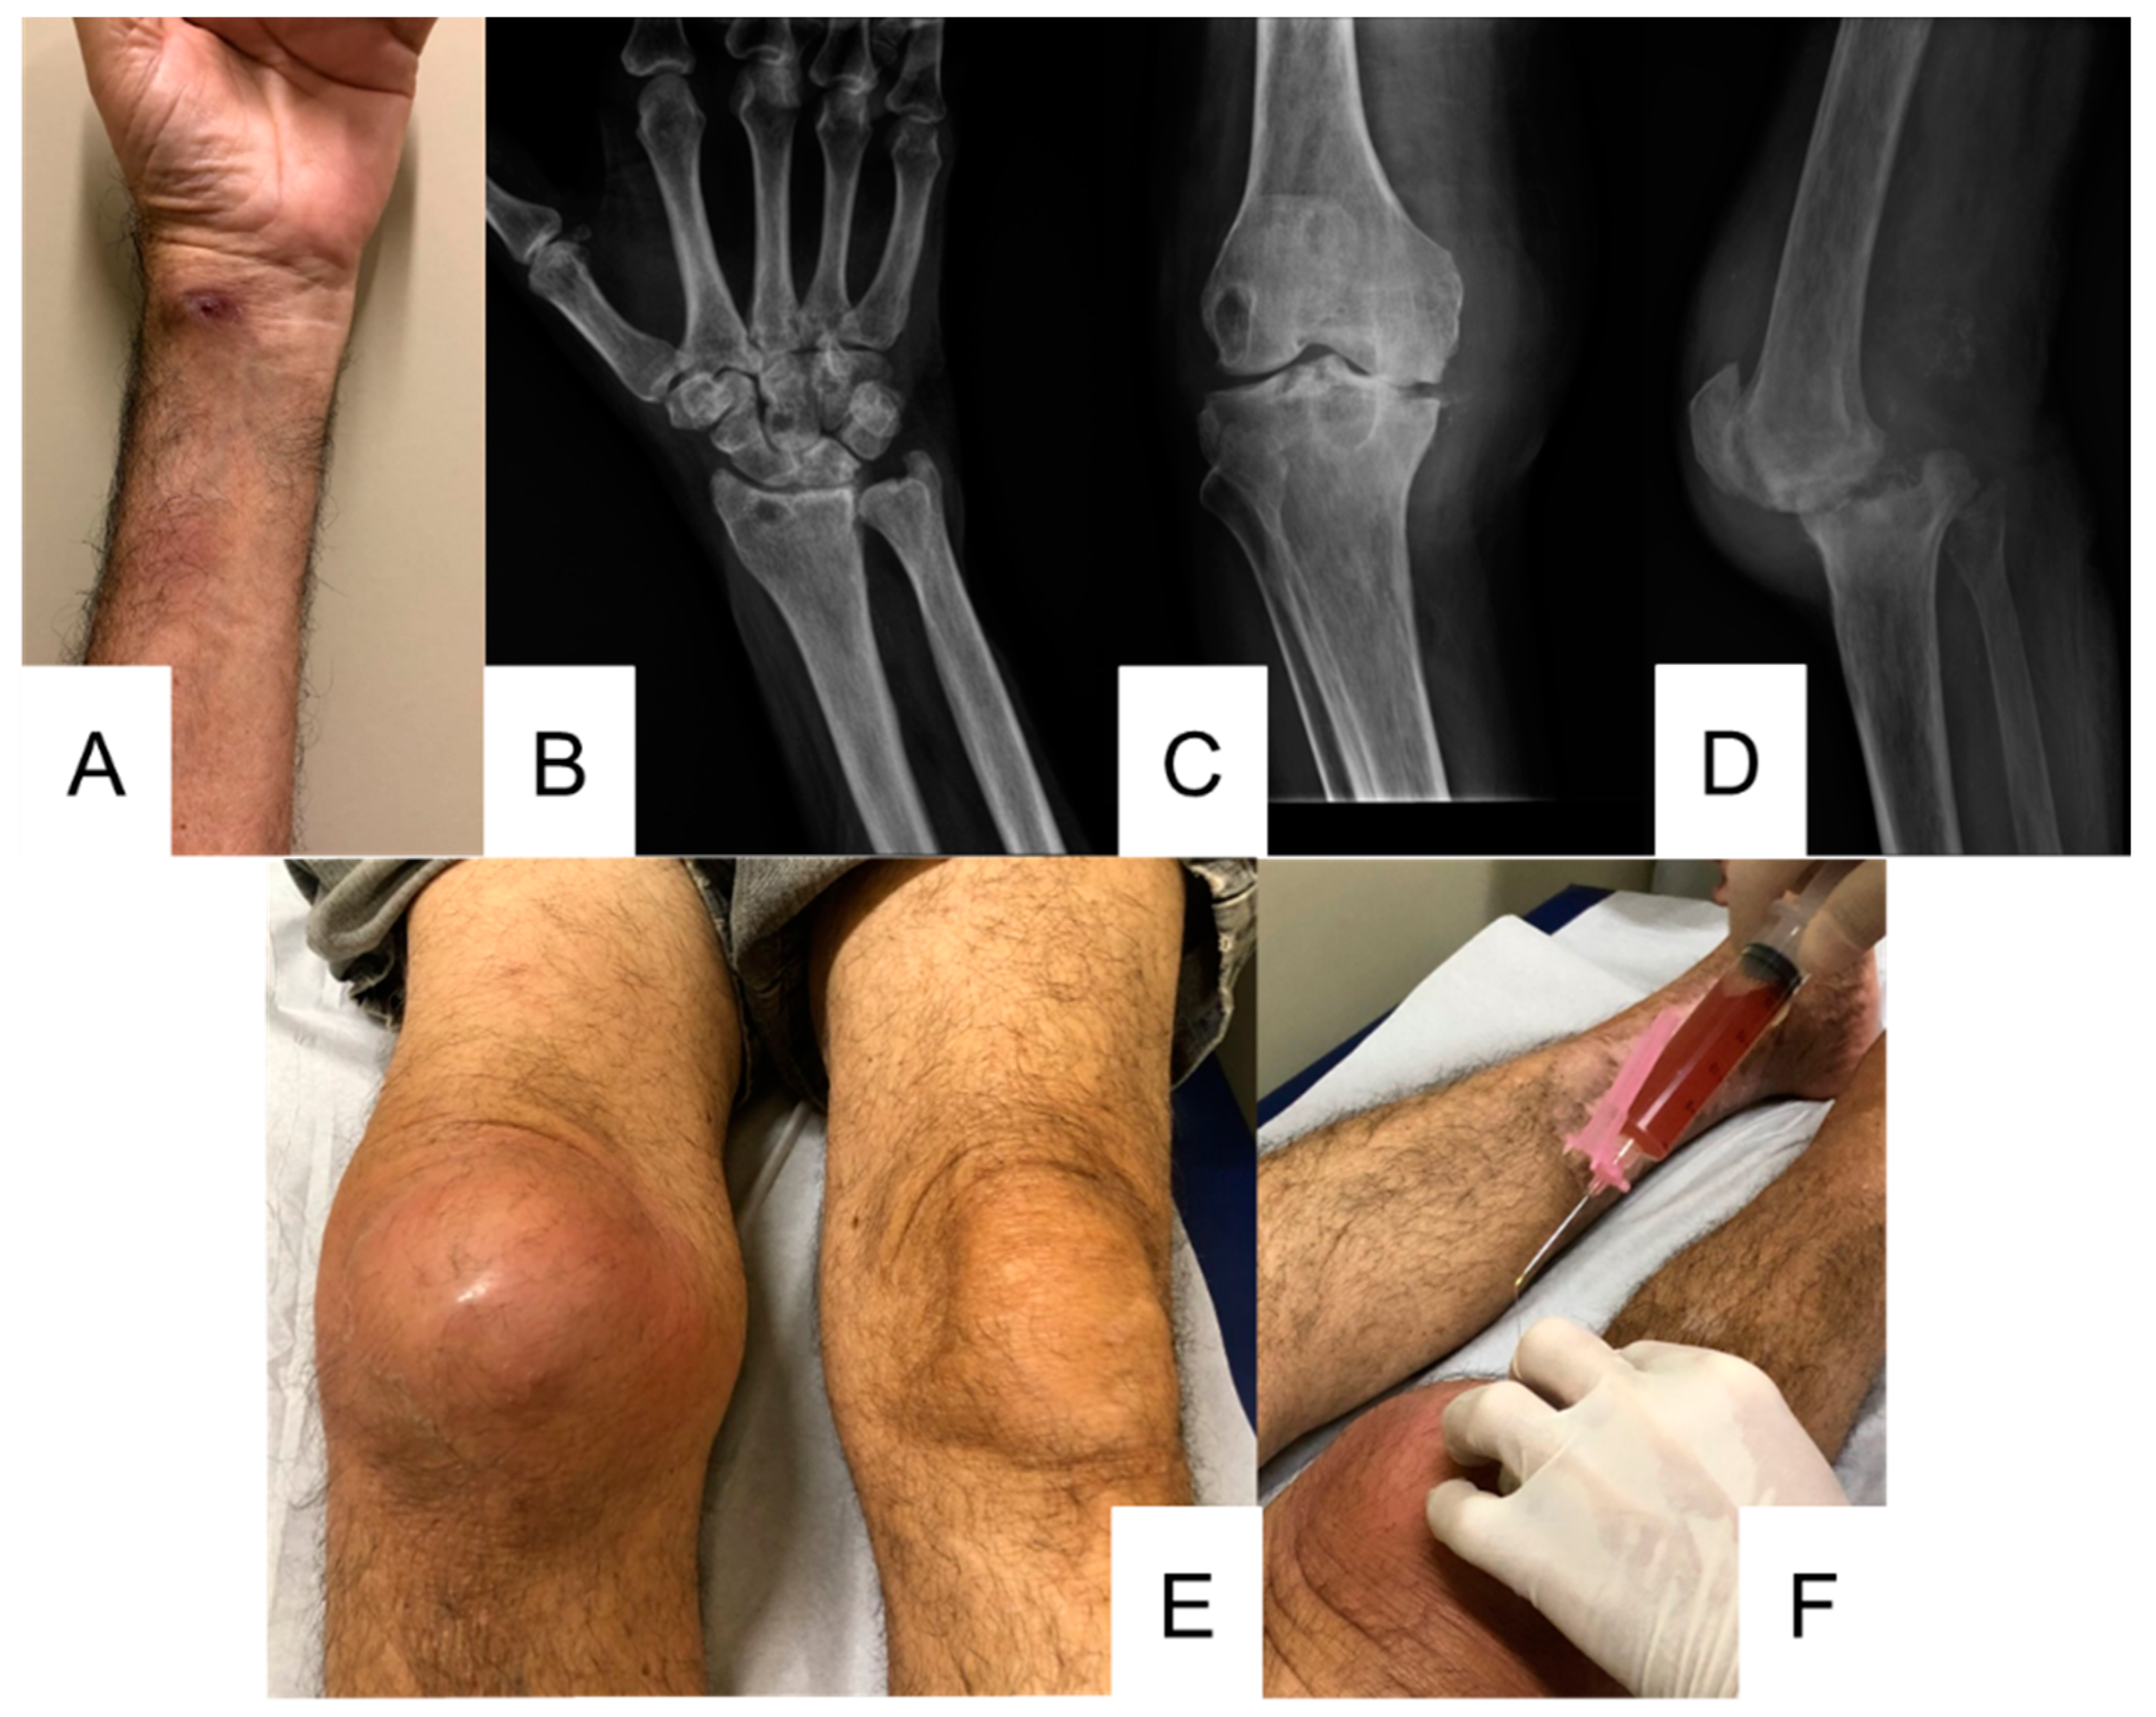

2.2. Patient 2